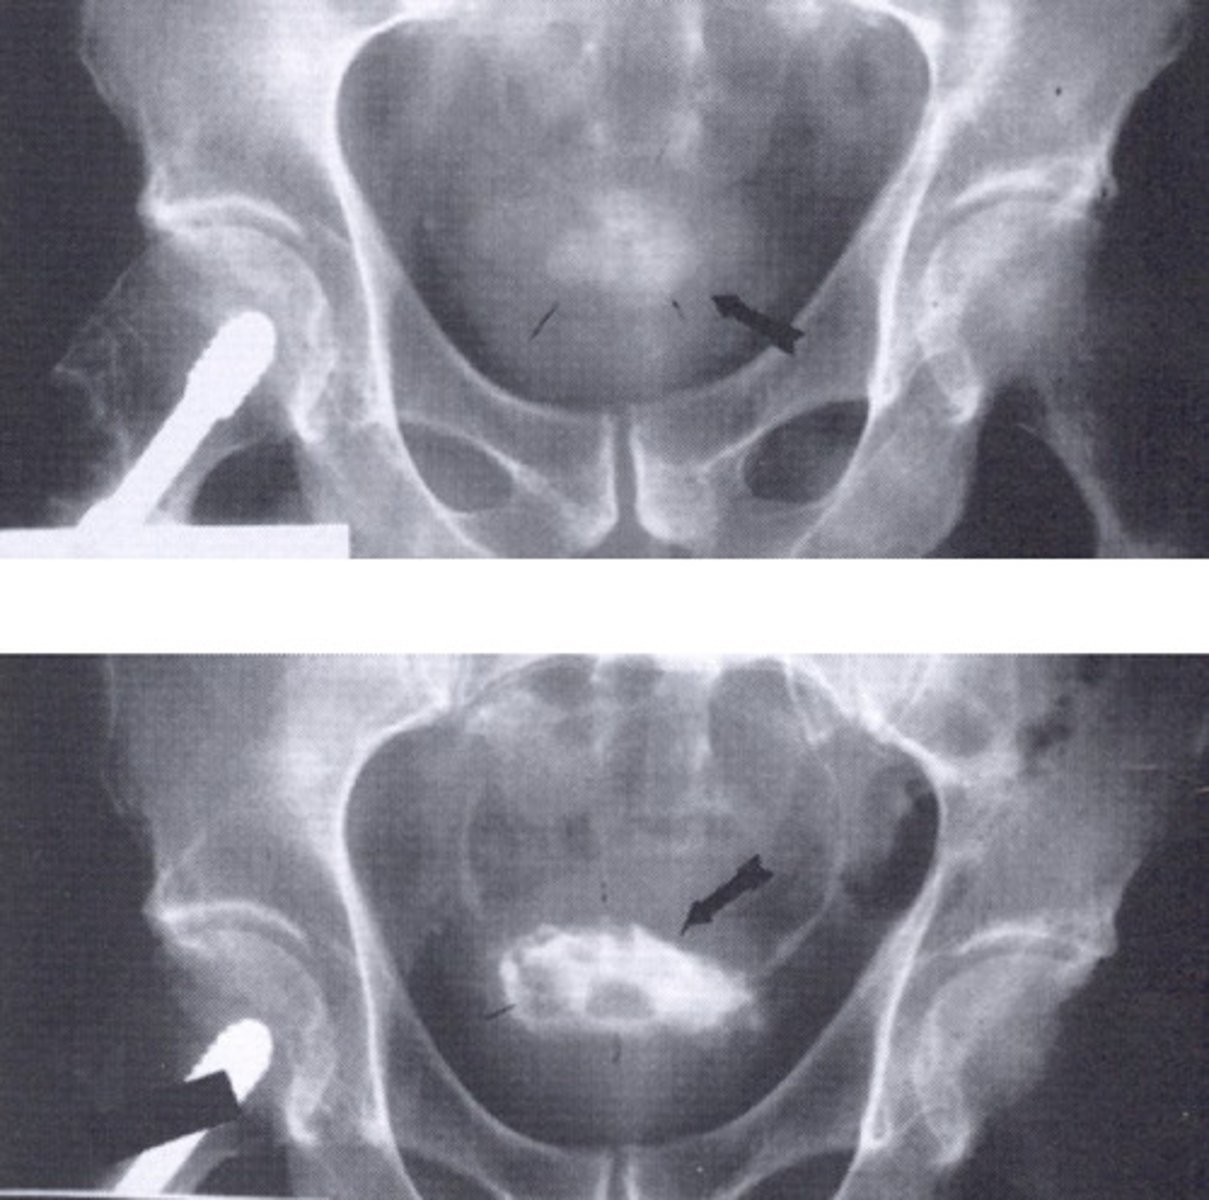

- Uteroceles

- "Cobra Head"

- With surgery

- What congenital anomaly refers to the cyst-like dilation of the distal ureter where it enters the trigone of the bladder?

- How does this pathology appear radiographically when the bladder is contrast-filled?

- How is this pathology treated?